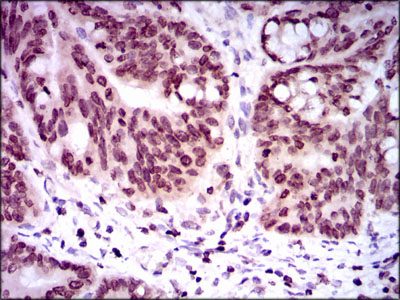

MCM7, Monoclonal Antibody (Cat# AAA25156)

KAP-1, Monoclonal Antibody (Cat# AAA25433)

MCM7, Monoclonal Antibody (Cat# AAA25450)

PRMT1, Monoclonal Antibody (Cat# AAA30343)